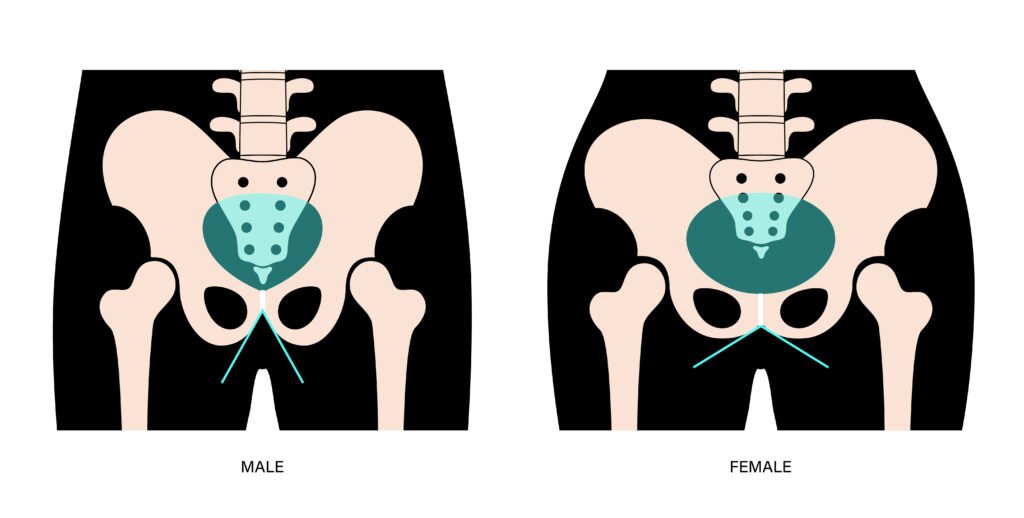

Differences between male and female hip anatomy

Your gender can influence how your hip is structured, and this is taken into account when planning surgery or rehabilitation.

Anatomy of a male and female hip

Pelvic differences

- Female pelvis: typically, wider and shallower, with a broader angle at the hips

- Male pelvis: usually narrower and deeper, with a more vertical alignment

These differences can affect how your muscles work and how load is transferred through your hip joint.

Fermoral Differences

- Women often have a smaller femoral canal and a slightly different angle at the femoral neck, which may impact implant sizing

- Men tend to have denser bone and larger femoral components

Dr Paterson uses these anatomical details to guide implant selection, surgical technique, and post-operative rehabilitation, ensuring your treatment is tailored to your body’s needs.